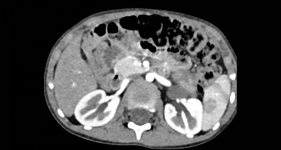

该患儿反复腹痛难忍,家属遂携其前往广元市第一人民医院就医。经检查发现腹腔内长有一直径约10厘米的巨大肿瘤,肿瘤上极达左侧肾门、下极达左侧髂总动脉分叉平面,可见腹主动脉下端一分支动脉供血,肿瘤已严重挤压肾脏、输尿管、肠道等重要脏器,若不及时手术,将危及生命。但患儿年龄仅3岁,器官娇嫩、耐受度低,且肿瘤与腹腔大血管紧密粘连,手术分离难度极高,稍有不慎便可能引发大出血等致命风险,治疗挑战重重。

面对这个棘手问题,医院立即启动儿童重症病例多学科协作机制。由分管副院长何东权主持,胃肠外科·小儿外科牵头,联合影像科、麻醉手术中心、心胸血管外科、儿科、肿瘤科、泌尿外科、重症医学科开展多轮会诊。影像科通过高清三维成像,精准标注肿瘤边界、血管分布及与周围脏器的关系,为手术规划“导航图”;麻醉手术中心针对患儿生理特点,定制“精准麻醉”方案,全程守护心肺功能稳定;重症医学科提前备好术后监护设备,做好应急保障预案。